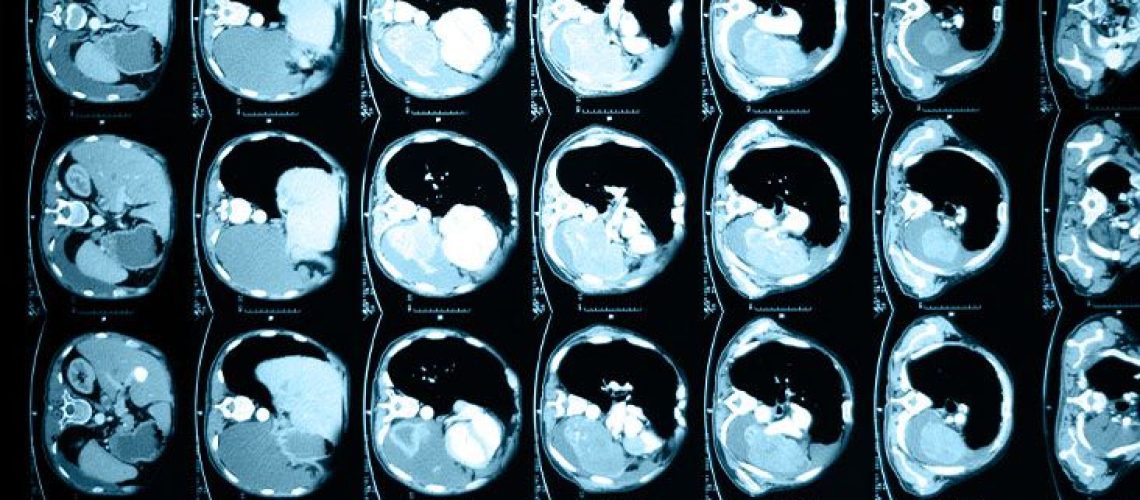

במחקרם, החוקרים בחנו את הכבדים של עכברים שהיו במשקל טיפוסי והשוו אותם לכבדים של עכברים עם השמנת יתר לאחר תקופות של האכלה וגם צום. הם אספו נתונים על תהליכים ביולוגיים שונים מחמש קבוצות של עכברים. לאחר מכן, הם שילבו את הנתונים שלהם עם מידע ממאגרי מידע ביולוגיים כדי להבין כיצד שכבות שונות של תהליכים מתקשרים.

למרות שהחוקרים בדקו כיצד כבדים של עכברים הושפעו, הם אמרו שהם ציפו שתוצאות דומות יתרחשו בבני אדם.